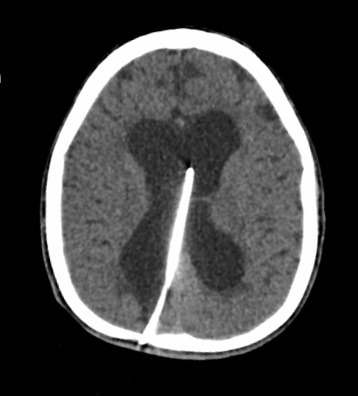

Objective: Normal embryonic and fetal development is strictly bound to maternal health and functioning placenta. Besides the invasion and differentiation of trophoblastic cell lineage; development of effective vasculature is crucial for the function of placenta. Placental vessels first arise by vasculogenesis in early development of villi and then succeeded by angiogenesis during fetal life. In the recent decades a new form of angiogenesis, “intussusceptive angiogenesis”, besides classical sprouting angiogenesis is well documented. The presence of intussusception was shown at multiple organs but in placenta, in recent literature. We aimed to determine whether intussusceptive angiogenesis is present in human placenta to obtain further evidence on the development of vascular bed. Methods: The term placenta samples were obtained from 10 healthy pregnancies following caesarean sections. Tissues were processed using routine plastic embedding technique; thin sections were contrasted with uranyl acetate & lead citrate; observed and photographed by transmission electron microscope. Results: Our examinations revealed that both sprouting and intussusceptive angiogenesis is present in floating villi of term placenta. Phases of intussusception were documented in various samples. Conclusion: The presence of intussusceptive angiogenesis will help our understanding of microvascular bed remodeling during pregnancy. We believe that this new finding will help us to determine the relation of microvascular bed development in normal and abnormal placentas.